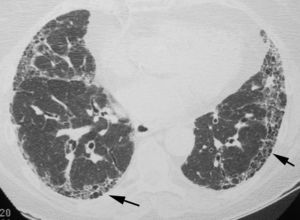

The objective is to identify findings typical of the UIP pattern (Fig. 3), and to distinguish them from the less specific patterns present in other idiopathic interstitial pneumonias. To prevent descriptive and conceptual errors, the radiological reading should use descriptive terminology based on the radiological–pathological correlation, as recommended by the Fleischner Society.22

The official 2011 ATS/ERS/JRS/ALAT consensus2 established that in HRCT, the definite diagnosis of UIP is based on the identification of four “typical” findings: (1) lung involvement should have subpleural and basal predominance, (2) presence of obvious reticulation, (3) existence of honeycombing with/without traction bronchiectasis/bronchiolectasis and (4) demonstrate the absence of findings considered to exclude a UIP pattern (Table 1, Fig. 3). The presence of ground glass opacities should be minimal or non-existent.

Honeycombing, made up of groups of thin-walled cysts, subpleural with a diameter between 3 and 10mm, is an essential finding for accurately diagnosing the UIP pattern. When there is no visible honeycombing, the diagnosis by HRCT will be that of a possible UIP pattern; in these cases, the definitive diagnosis of UIP should be made by biopsy. Lung biopsy can be avoided only when the HRCT shows a definitive pattern, typical of UIP. The positive predictive value of HRCT in the diagnosis of UIP is 90%–100%. A UIP pattern can also be identified in chronic hypersensitivity pneumonitis, asbestosis and some connective tissue diseases.23